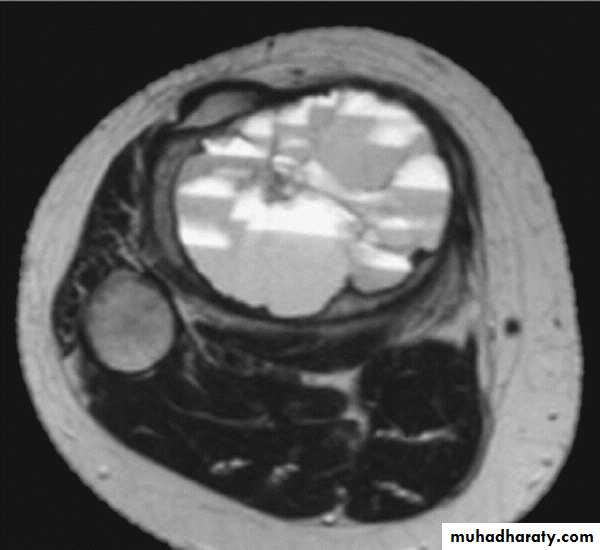

MRI